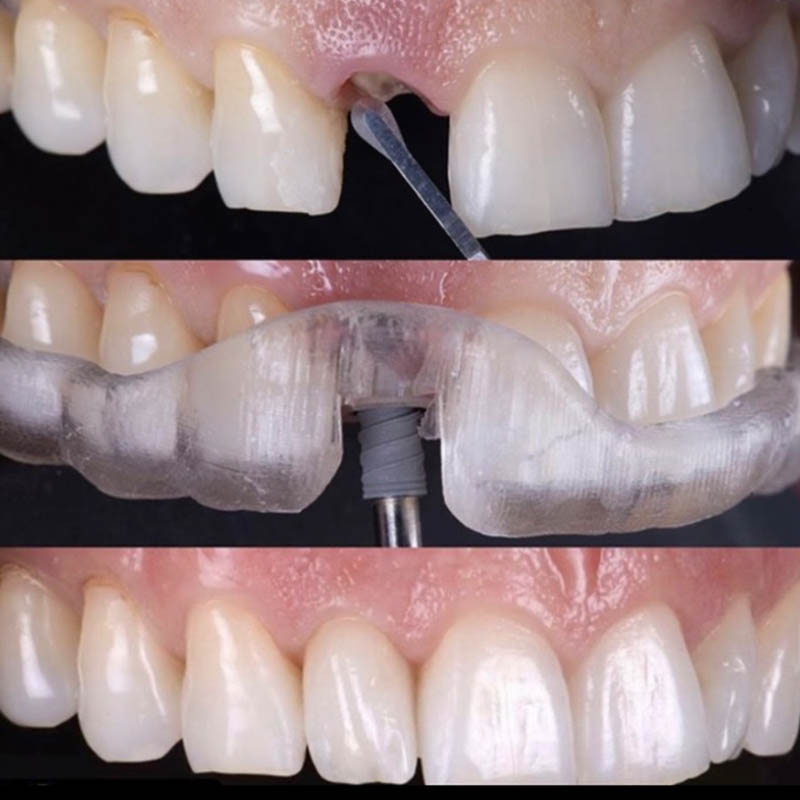

На современном этапе достичь нужного результата стоматологического лечения нередко удается только путем дентальной имплантации. Специалисты клиники Совершенная улыбка тоже активно используют данную методику. При этом в своей деятельности они располагают всеми предпосылками для проведения как быстрой имплантации, когда все действия врач завершает в течение одного посещения, так и операции по классической методике, которой предшествует целый ряд подготовительных процедур, костная пластика.

Успех имплантации в клинике обеспечивается не только мастерством специалистов, высоким уровнем диагностических мероприятий, но использованием качественных материалов, отлично зарекомендовавших себя в сложных клинических случаях или при недостаточной плотности костной ткани. В совокупности такие предпосылки позволяют сократить противопоказания к проведению операции, получить отличные отдаленные результаты. При этом, стремясь обеспечить каждого пациента самым эффективным результатом ортопедического лечения, что гарантирует имплантация, наши специалисты имеют возможность проводить ее моделями разных ценовых категорий. Столь привлекательные финансовые условия позволяют воспользоваться данной методикой людям с любым уровнем доходов.

Примеры работ